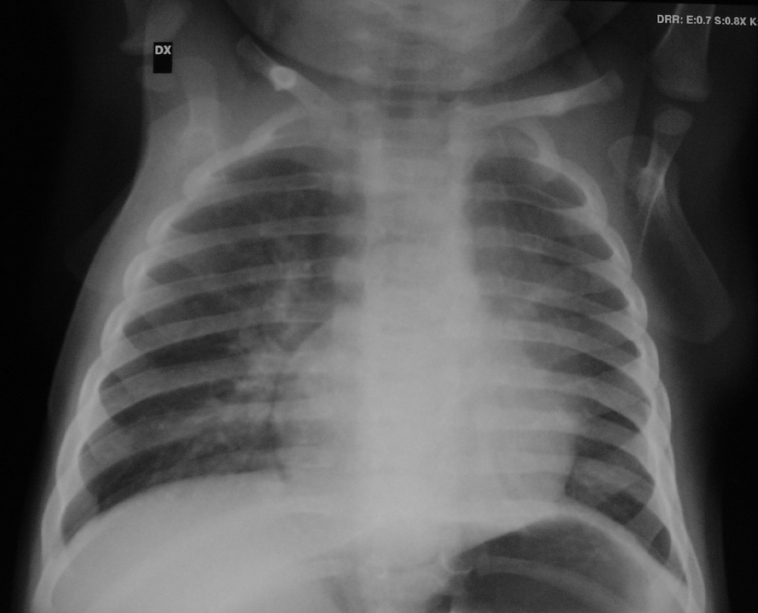

S. � un bambino di 4 anni in cui era stata fatta diagnosi prenatale di malformazione basale sinistra alla 23� settimana di gestazione. A fine gravidanza la lesione non era pi� visibile per cui, dopo la nascita non era pi� stata ricercata. Dall�et� di 2 anni, tuttavia erano comparsi episodi polmonari infettivi recidivanti sempre alla base inferiore di sinistra.

L�Rx torace eseguito in corso di uno di questi episodi aveva evidenziato la presenza di polmonite basale sinistra (Figura 1).

La TAC, eseguita a risoluzione del terzo episodio infettivo, metteva in luce la presenza di lesione malformativa, altrimenti non visibile in radiologia convenzionale (Figura 2).

All�et� di 4 anni il bambino veniva sottoposto a intervento di lobectomia inferiore sinistra per via toracoscopica.